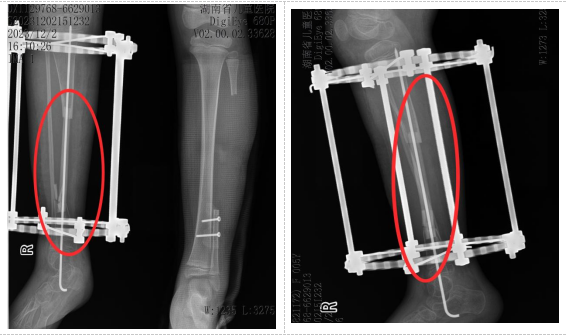

经过两年定期复查,影像学检查证实,移植的腓骨已在新的位置“安家落户”,与胫骨牢固愈合,直径明显增粗,具备了良好的承重能力。小小的右下肢长度得到维持,功能恢复良好,生活质量得到了显著改善。

术后两年